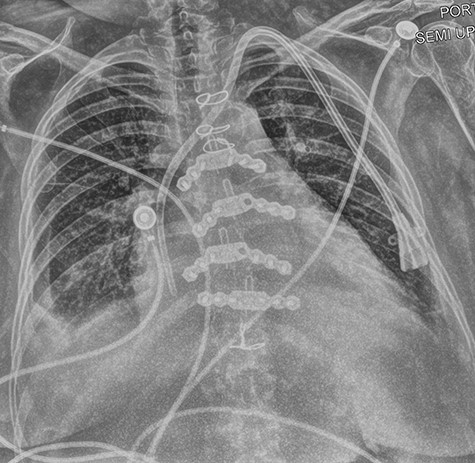

After uncomplicated induction of anesthesia, the patient was anticoagulated with 4000 units of intravenous heparin. The right internal jugular dialysis catheter was removed over a wire placed into the superior vena cava. A large clot was detected in the right subclavian vein, which was treated with angioplasty via the cephalic vein using a 14-mm balloon, resulting in improvement in venous flow. Both access points were closed, and anticoagulation was reversed with 25 mg protamine sulfate 65 minutes after initial heparin bolus. The surgical team then encountered resistance while placing a microwire via the left internal jugular vein into the left subclavian vein for left dialysis catheter placement. After several attempts, the wire was placed under fluoroscopic guidance and the dilator was advanced. During dilator advancement, seen in Fig. 1, resistance was encountered at the cavoatrial junction. Immediately thereafter, the patient experienced profound hypotension and received cardiopulmonary resuscitation (CPR). Intraoperative transesophageal echocardiography imaging demonstrated pericardial tamponade with partial clot. The surgeon obtained large bore vascular access and placed an arterial line in the femoral artery. CPR was stopped after return of spontaneous circulation, with the patient being responsive to vasopressors and further resuscitated with 9 units packed red blood cells, 9 units fresh frozen plasma and 2 units of platelets.

Digital subtraction angiography from operating room fluoroscopy.